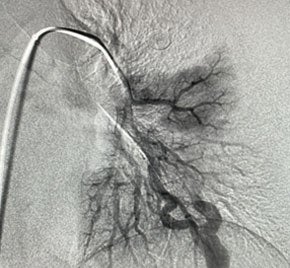

An 8 F guiding catheter, 4 F diagnostic catheter and a Direxion HI-FLO microcatheter were placed in the left-sided AVM. Two 14 mm Embold Fibered Coils were placed in the 11 mm nidus, and 10 mm and 8 mm coils were placed in the feeding vessel.

The AVM was successfully embolized with Embold Fibered Coils.

300x300 After Embold Fibered placement​